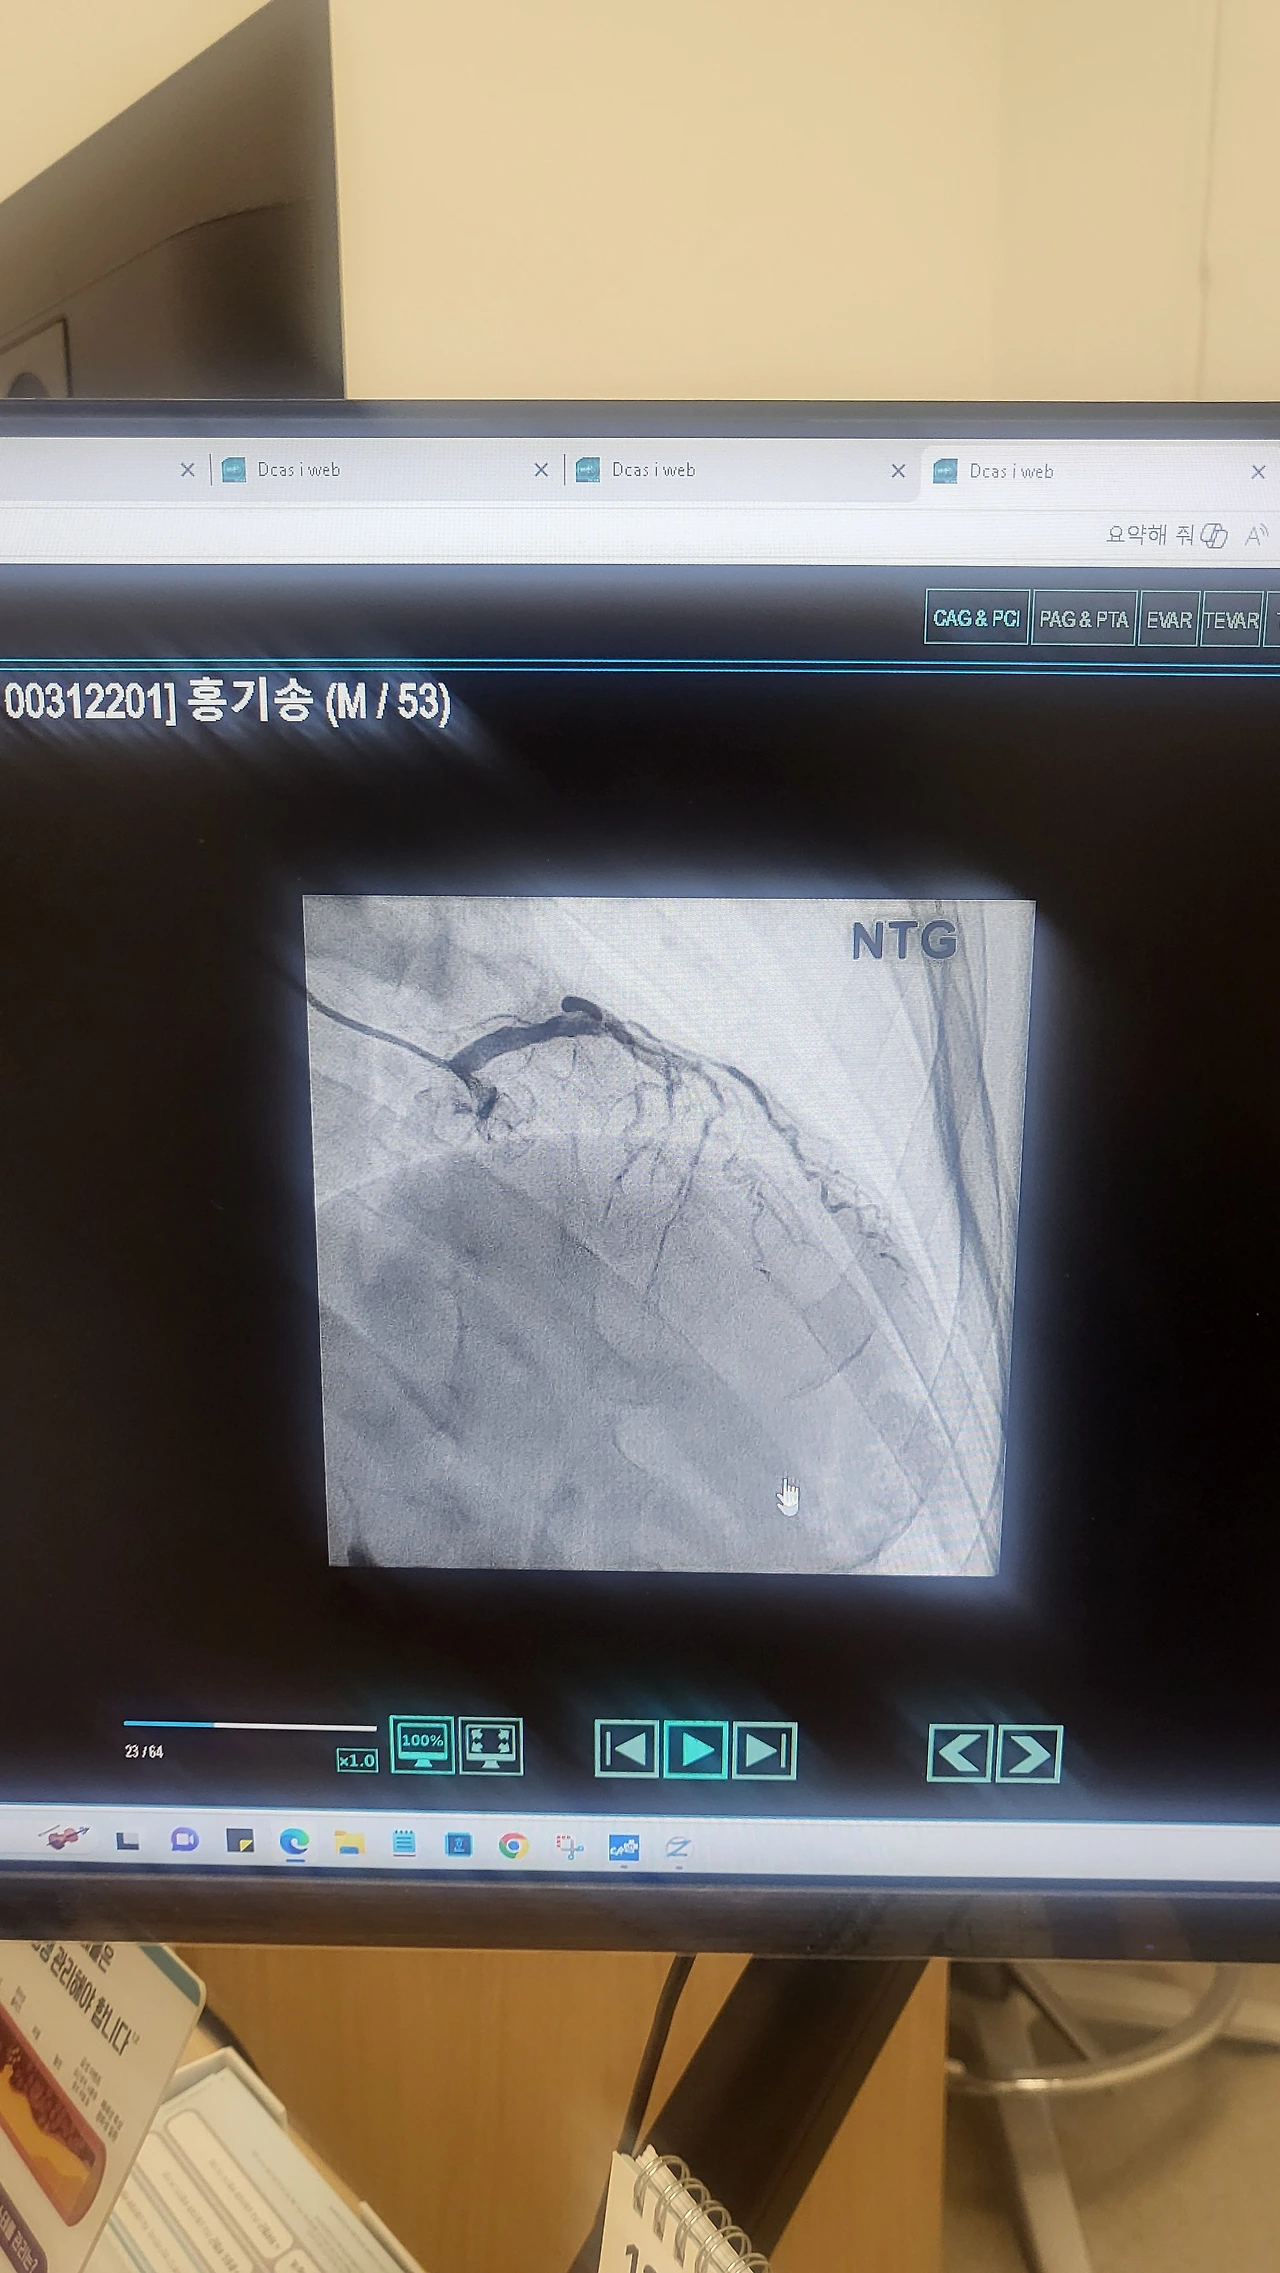

좁아진 줄 알았던 1번 관내동맥이 완전히 막혔다고 했다. 서서히 막혀서인지, 심장이 스스로 살기 위해 다른 작은 혈관들이 새로운 혈관을 만들었다고 했다. 그 덕분에 지금까지 통증 없이 살아 있다고 했다.

혈관이 막혔다는 이야기를 듣고 심장박동수가 빨라졌다. 의사는 지금 당장 급한 건 아니지만 이왕 여기 가지 왔으니 막힌 혈전을 뚫어보겠다고 했다. 설명을 쉽게 해 주려는 것인지, 터널 뚫는 것과 같은 거라며, 걱정하지 말라고 했다.

처음에 왼쪽 손에만 꽂혔던 와이어가 막힌 혈전을 뚫으면서 오른쪽 손에도 연결이 되었다. 그때부터 모니터에서 삐삐 들려오는 소리와 혈압측정기 소리, 의사들이 나누는 알 수 없는 대화들과 간혹 간호사가 불편하지 않냐고 물어보는 소리들이 들려왔다.

가슴 위로는 정사각형의 CT기계가 심장으로 흐르는 혈관들을 계속 찍고 있었다. 누워있는 침대 옆으로 커다란 모니터가 심장 속 혈류의 흐름을 사진 찍듯이 선명하게 보여주고 있었다. 조영제가 들어갈 때 막힌 곳과 좁아진 곳의 위치가 정확히 드러났다. 마치 자동차 안에서 보는 내비게이션처럼, 얽혀있는 심혈관들의 혈류가 강물 흐르듯 흐르고 있었다.